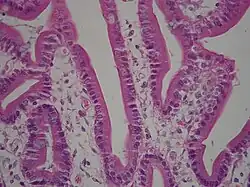

Клетки однослойного призматического эпителия имеют удлинённую форму, их яйцевидные, нередко также удлинённые ядра, как правило, располагаются на одном уровне в базальных частях клеток[20]. Однослойный призматический эпителий характерен для многих отделов пищеварительного тракта — желудка, тонкого и толстого кишечника, жёлчного пузыря, некоторых протоков печени, поджелудочной железы и некоторых других желёз. Апикальные поверхности клеток несут микроворсинки. Многочисленные контакты между эпителиоцитами, выстилающими пищеварительный тракт, не дают выйти в полость тела содержимому соответствующих органов[27]. Клетки однослойного призматического эпителия, который выстилает матку, яйцеводы и мелкие бронхи, несут реснички[24]. Ресничный призматический эпителий выстилает изнутри спинномозговую полость и желудочки головного мозга[28].